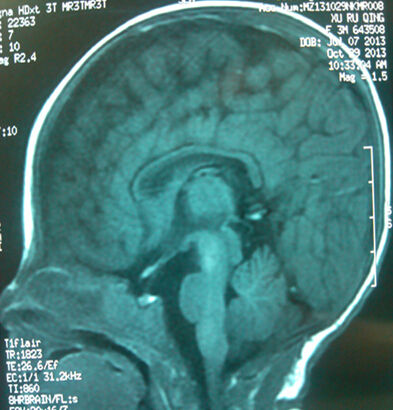

这是一位男孩,37周,于2012.5.23剖宫产,出生体重2700克,出生时无窒息,生后4天来就诊。头颅MRI显示颅内出血Ⅲ°,胼胝体缺如。开始指导早期干预。3个月29天视听反应好,头竖立时晃动,余神经运动检查未见异常。10.5月视听反应好,头竖立时晃动,余神经运动检查未见异常,智测DQ84.5。1.5岁时,独走自如,能说单词,神经运动检查未见异常,智测DQ96.3。

胼胝体是大脑左右半球联系的神经纤维组成的大脑重要结构。上面报告的病孩出生时胼胝体缺如。但是,他到1.5岁时运动和智力完全正常。大脑就有这么神奇的代偿能力。